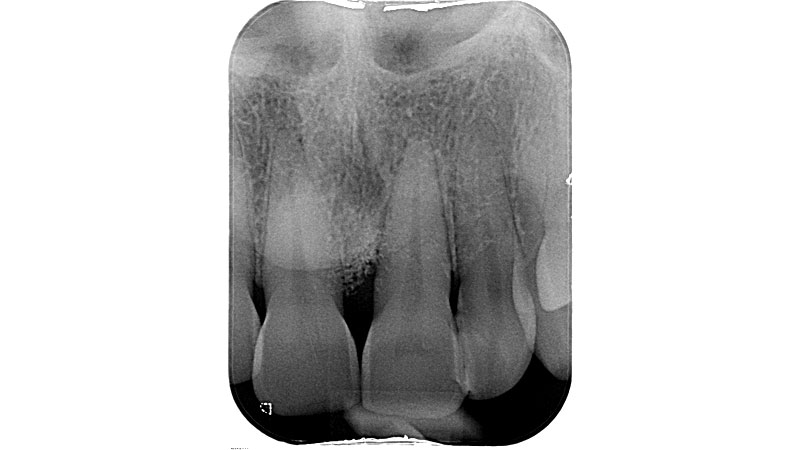

01/11 - Pre-operative radiograph.Non-contained intrabony defect treated using cerabone®, collprotect® membrane and Straumann® Emdogain® - Dr. T. Schwaar (2)